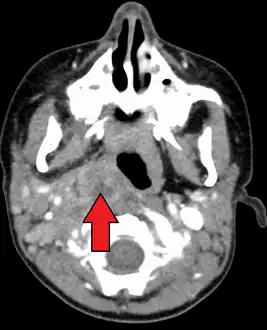

A computed tomography (CT) scan is the definitive diagnostic imaging test.[4]